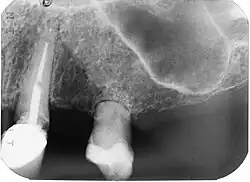

X-Ray of affected tooth (incisor 9, left).